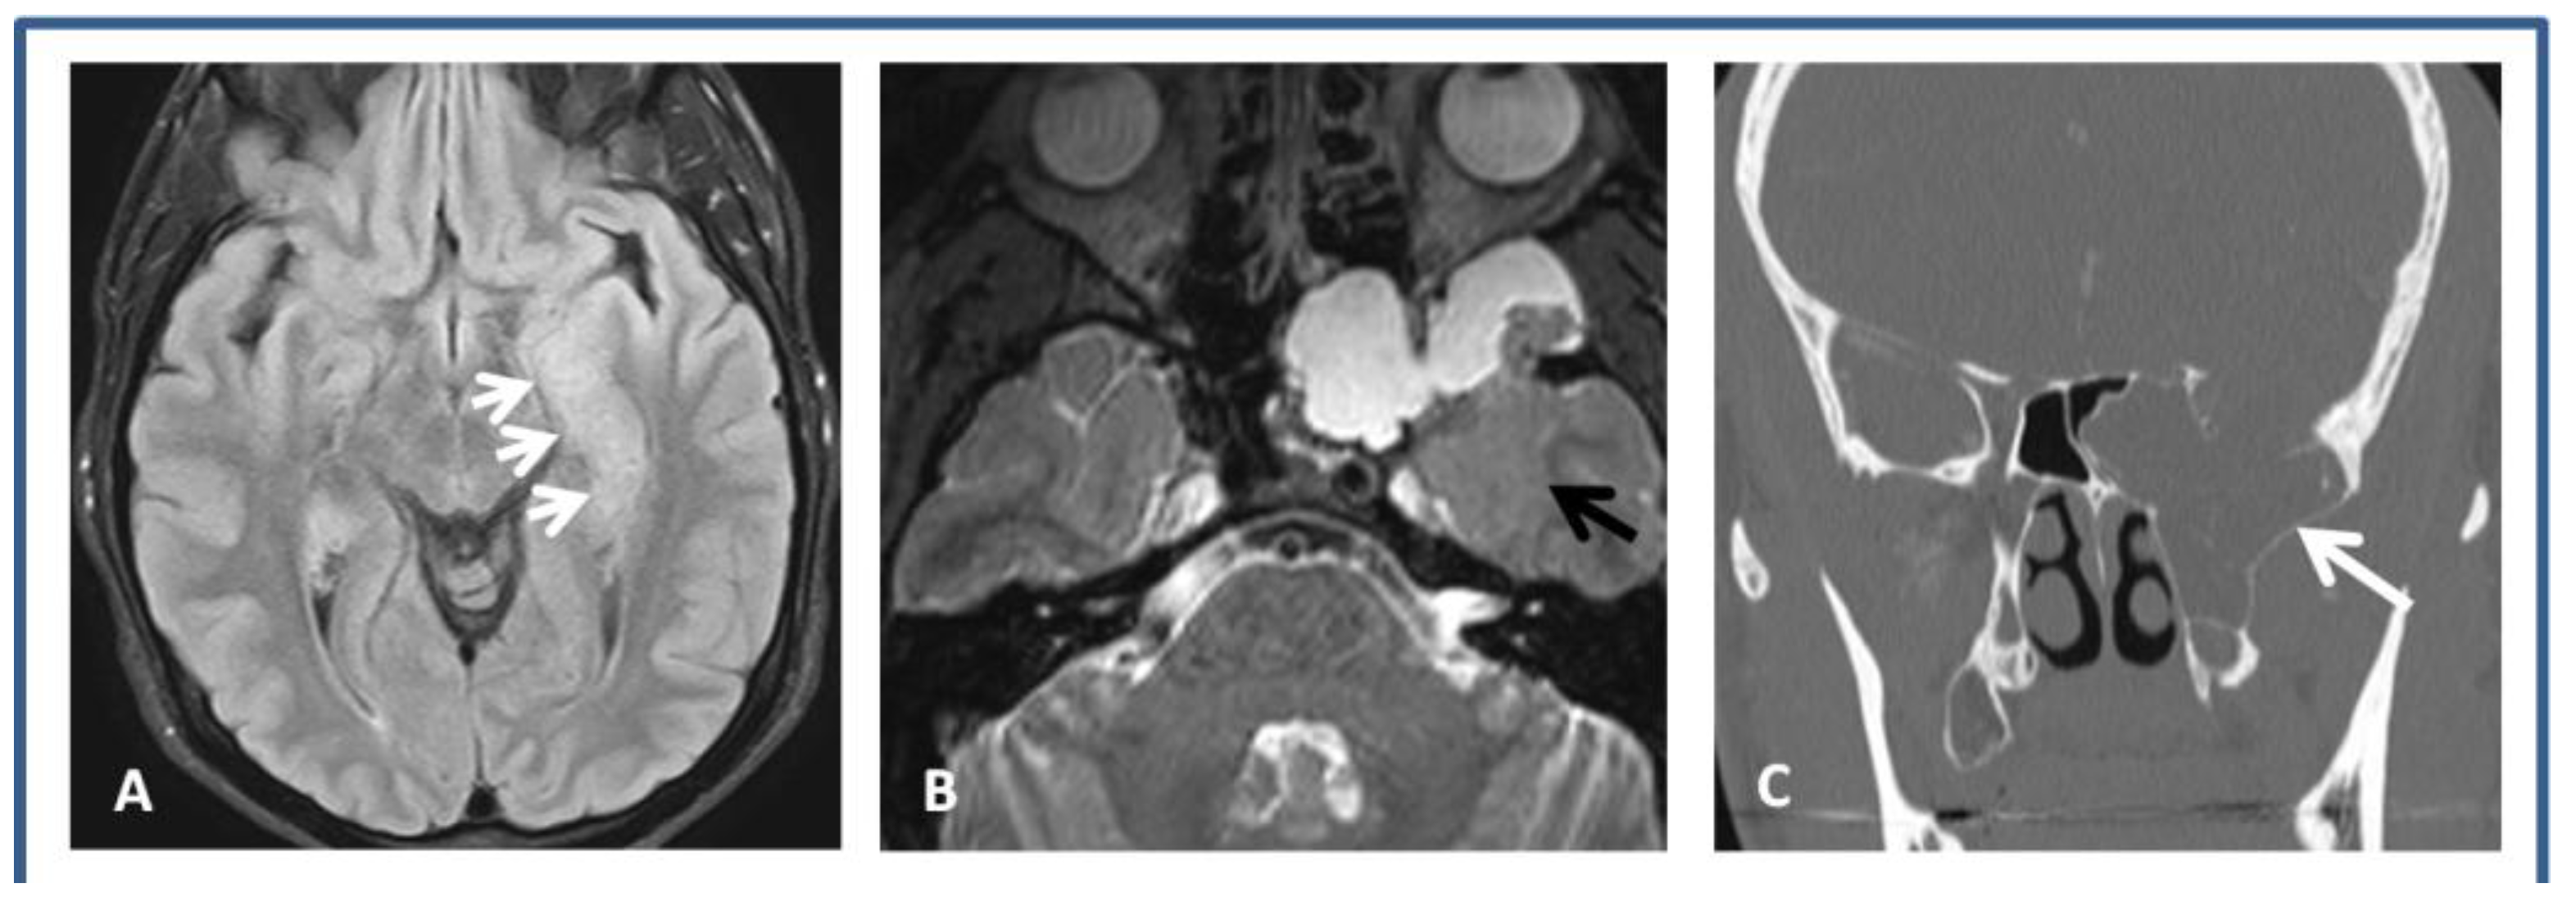

2.1. Case 1: 24-Year-Old Ambidextrous, Bilingual (English and German) Man with Seizures Since 22 Years of Age. Seizure Semiology: Ictal Expressive Aphasia, Right Forced Head and Eyes Deviation, Lip-Smacking, and Sensation of Fear

2.2. Case 2: 66-Year-Old Right-Handed Man with Intractable Epilepsy since the Age of 43 Years, after He Was Struck on Forehead at Work by a Pump While Pumping Oil from a Compressor. Seizure Semiology Consisted of Dizziness, Starring Off, Lip-Smacking, Excessive Drooling, Right Hand Rolling Movements, and Occasional Bilateral Tonic-Clonic Seizures